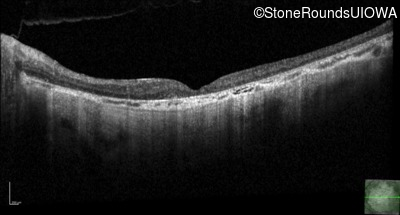

Optical Coherence Tomography - Right - 20/250 sc

Exemplar / OCT Stack